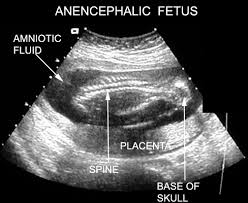

penyakit nie dinamakan ANENCEPHALY..

anencephaly bermaksud "tanpa adanya encephalon"..

bayi dilahirkan tanpa kulit kepala, tempurung kepala, hemisphere otak dan cerebellum..

penyakit nie bleh dikesan pada awal kandungan..